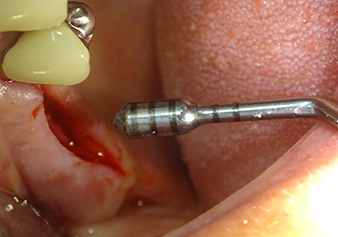

The I2A instrument (diameter 2.0 mm) was then used to perforate the sinus floor intermittently and on the smallest scale possible. This special piezosurgical method ensures that the Schneiderian membrane is not damaged. When the Z25P was used, the membrane was already lifted slightly by the coolant supplied via the instrument tip (Fig. 3). The coolant quantity was just 50% in order to avoid high pressure in the implant bed.